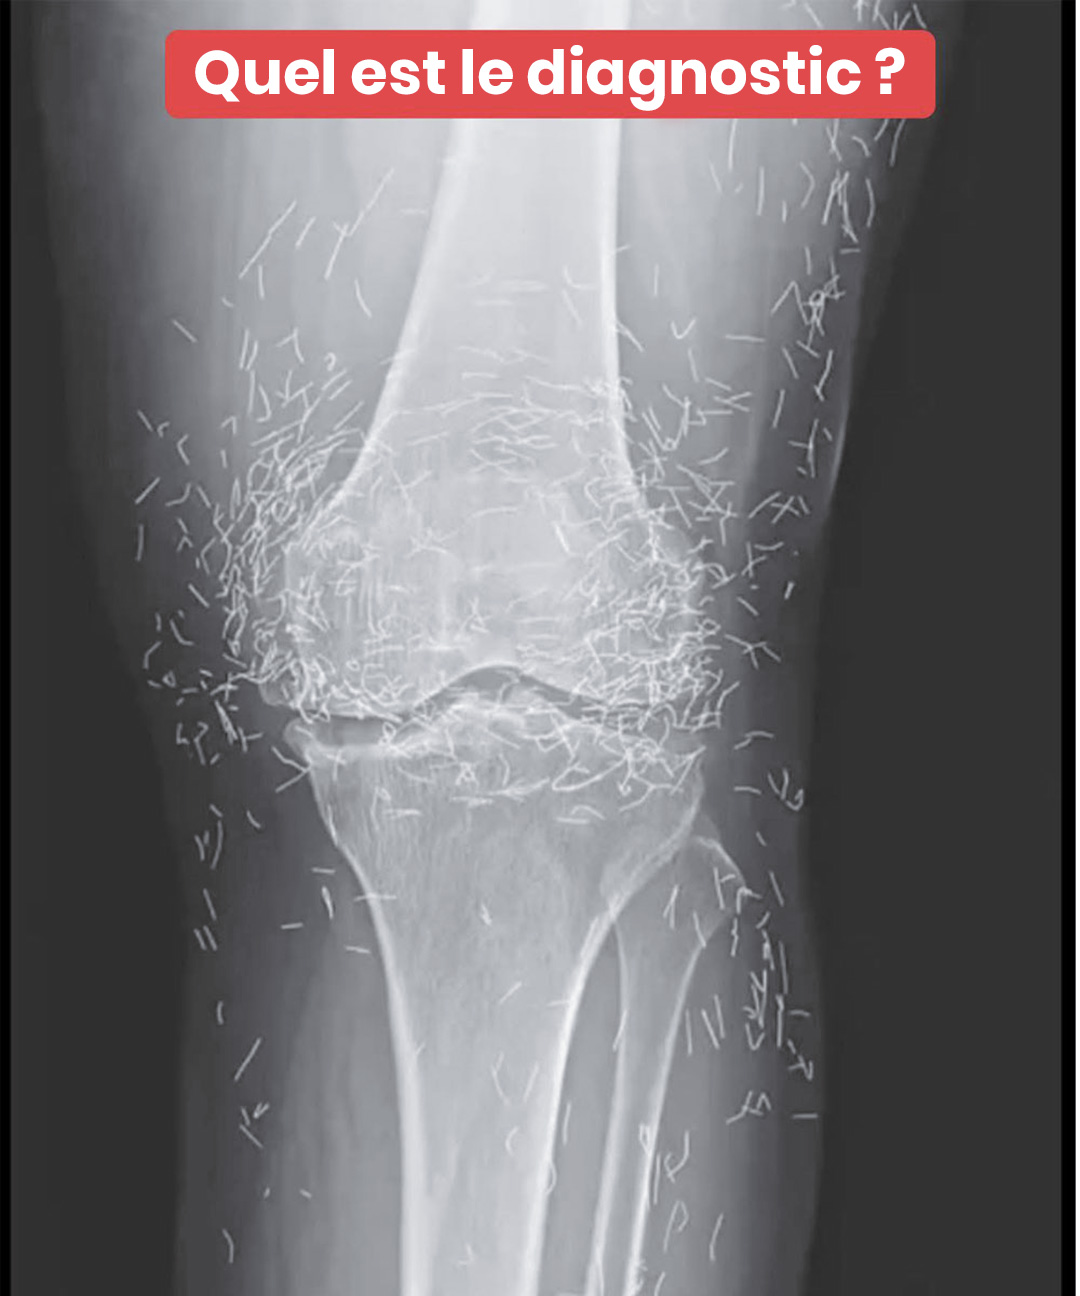

Les genoux d’une femme révèlent, à la radiographie, la présence de centaines d’aiguilles en or

Imaginez passer une simple radiographie pour des douleurs aux genoux… et découvrir que votre corps renferme un véritable trésor caché ! C’est ce qui est arrivé à une femme de 65 ans, dont les clichés médicaux ont révélé une présence pour le moins inattendue. Ce que les médecins ont vu a soulevé bien plus de … Lire plus